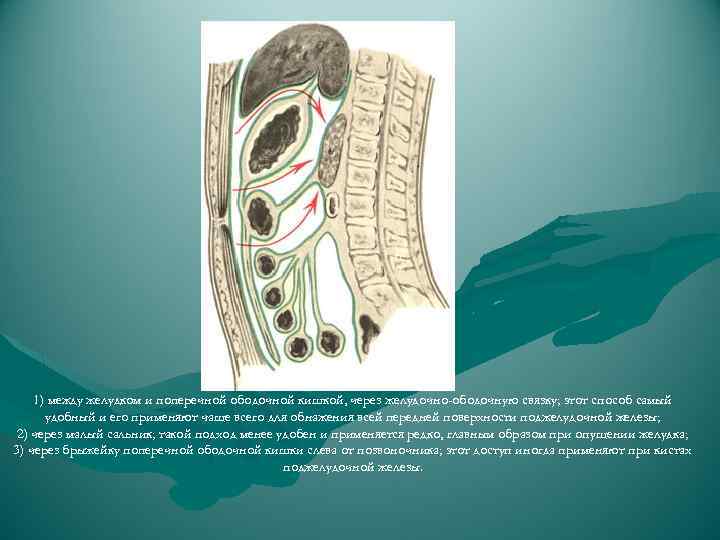

1) между желудком и поперечной ободочной кишкой, через желудочно-ободочную связку; этот способ самый удобный и его применяют чаще всего для обнажения всей передней поверхности поджелудочной железы; 2) через малый сальник; такой подход менее удобен и применяется редко, главным образом при опущении желудка; 3) через брыжейку поперечной ободочной кишки слева от позвоночника; этот доступ иногда применяют при кистах поджелудочной железы.

1) между желудком и поперечной ободочной кишкой, через желудочно-ободочную связку; этот способ самый удобный и его применяют чаще всего для обнажения всей передней поверхности поджелудочной железы; 2) через малый сальник; такой подход менее удобен и применяется редко, главным образом при опущении желудка; 3) через брыжейку поперечной ободочной кишки слева от позвоночника; этот доступ иногда применяют при кистах поджелудочной железы.